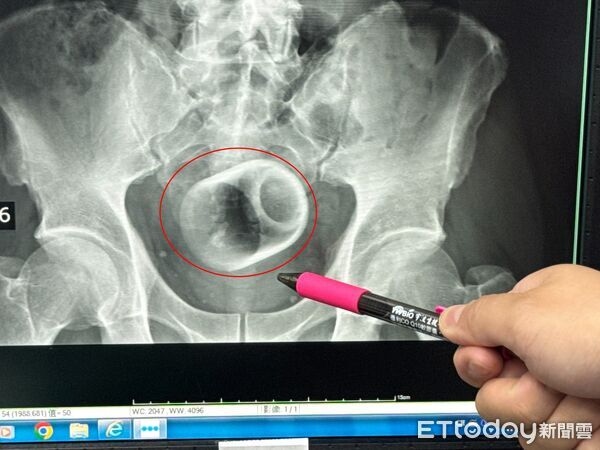

แกลเลอรีรูปภาพ ชายปวดท้องหนัก 3 วัน ถ่ายไม่ออก! หมอผงะ เจอ "ถ้วยเซรามิก 8 ซม." อุดช่องทวาร